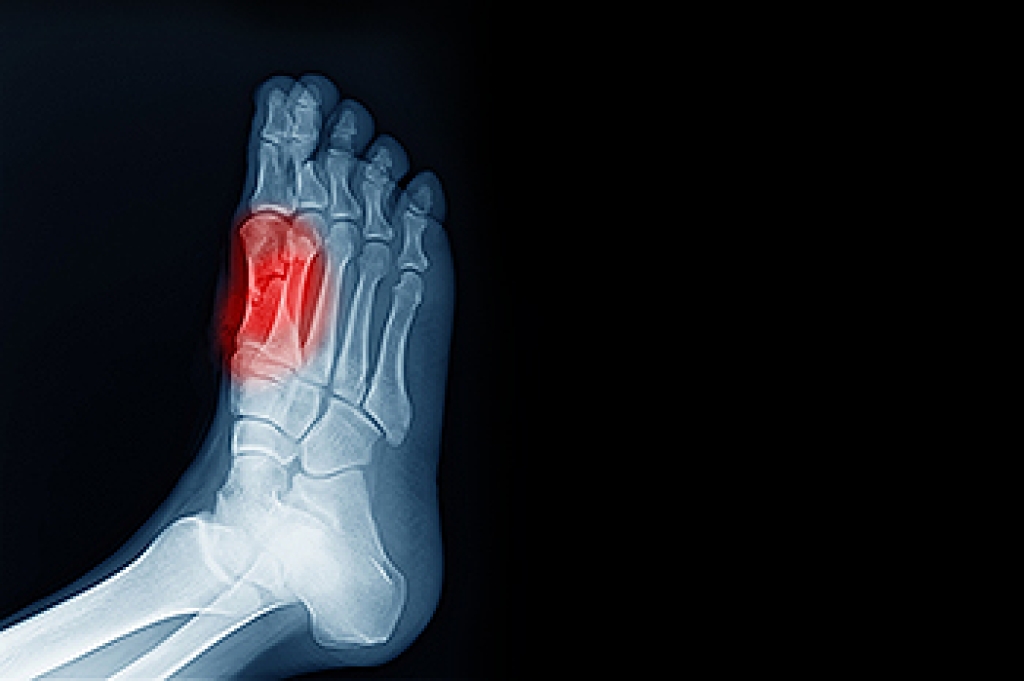

Diagnosis

Diagnosis of cuboid syndrome is often difficult, and it is often misdiagnosed. X-rays, MRIs and CT scans often fail to properly show the cuboid subluxation. Although there isn’t a specific test used to diagnose cuboid syndrome, your podiatrist will usually check if pain is felt while pressing firmly on the cuboid bone of your foot.